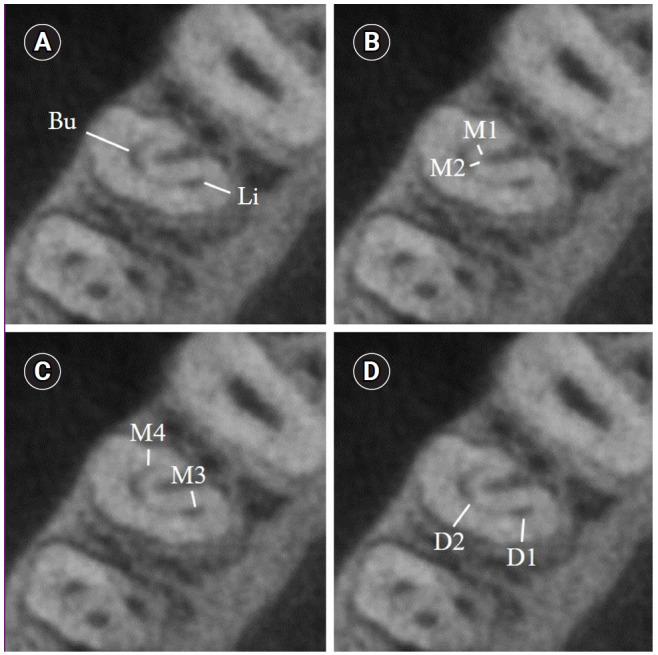

Methods: Dentin thicknesses of buccal, lingual, mesial, and distal root walls of 41 C-shaped premolars were measured at three different root levels on axial CBCT slices. The measurements were made at the midpoint of each third, along with 1 mm below and above the midpoint. C-shape configurations of the premolar root canals were also recorded. Analysis of variance, Kruskal-Wallis, and the independent samples t-tests were used for the comparisons (p = 0.05).

Results: The thickest walls for both premolars were buccal and lingual walls at all three root levels (p < 0.05). The thinnest walls for the first premolar teeth were mesial and distal walls of the lingual canal, while it was the mesial end of the buccal and lingual canals for the second premolars (p < 0.05). Dentin wall thicknesses at the mesial end of buccal and lingual canals of C1-shaped first premolars were thinner than C2-shaped first premolars at the apical level (p < 0.05).

Conclusions: Danger zones for C-shaped mandibular first and second premolars are predominantly mesial walls facing the radicular groove and distal wall of the lingual canal. CBCT imaging during endodontic treatment is recommended to avoid complications.